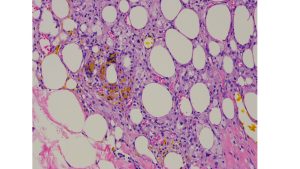

皮膚超音波検査では赤丸に包まれるやや低エコー性の境界明瞭な病変が観察される。黄色で包まれる底部では低エコーと連続する高エコーの領域が見られる。HE染色では低エコーの領域は脂肪組織で高エコーの領域は細胞成分が増している。細胞成分が増している領域は脂肪組織に対するマクロファージを主体とした肉芽腫性炎症が観察される。